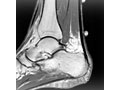

If your symptoms are severe or don't improve with treatment, your doctor may want you to get an X-ray, ultrasound scan, or MRI.

• MRI scan to check the tendon for signs of tendinopathy or a tendon rupture. An MRI is also used to evaluate the heel bone.